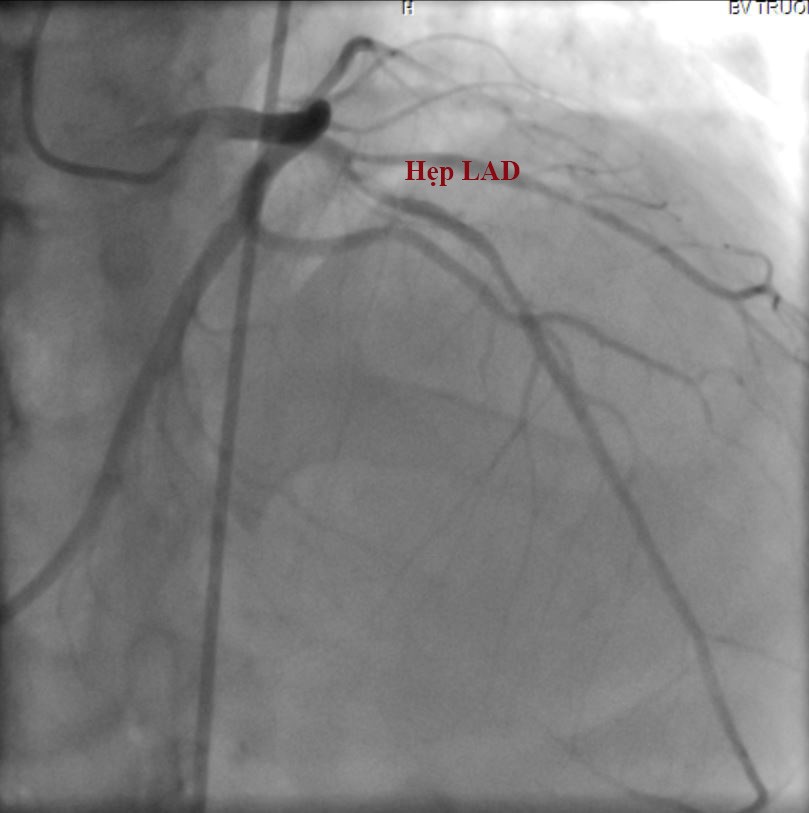

Chụp mạch vành chọn lọc cho

thấy chỉ có một động mạch vành trái xuất phát từ xoang động mạch vành trái, nó

chia thành 2 nhánh như bình thường là nhánh động mạch liên thất trước (LAD) và

nhánh động mạch mũ (LCx). Hẹp nặng 80% đoạn gần và 50% đoạn giữa của động mạch

liên thất trước (hình 1). Hình ảnh động mạch chủ không có sự hiện diện của động

Hình

1. Hẹp động mạch liên thất trước